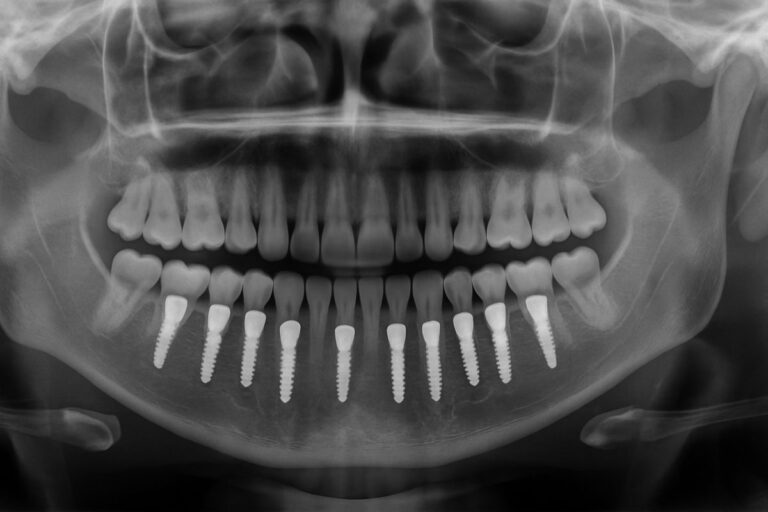

Dental Implants Cleveland OH: Options, Costs, and How To Choose

If you’re researching dental implants as a lasting solution for missing teeth, this guide covers options, costs, and how to choose dental implants in Cleveland